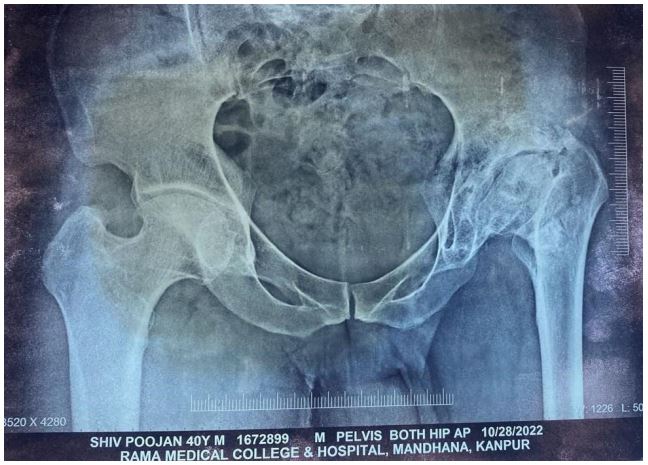

X-ray pelvis with hip ap view s/o-shallow acetabulum, pseudo acetabulum, subchondral sclerosis, deformed femoral head, reduced joint space, over-riding of GT, narrow femoral canal (Dorr type I) (Figure 1). Preoperative templating is done, it helps in knowing appropriate size of femoral and acetabulum component. The acetabulum and femoral bone stock are assessed by hip X-rays.

Figure 1: Pre-op x-ray of the pelvis with both hip AP view.